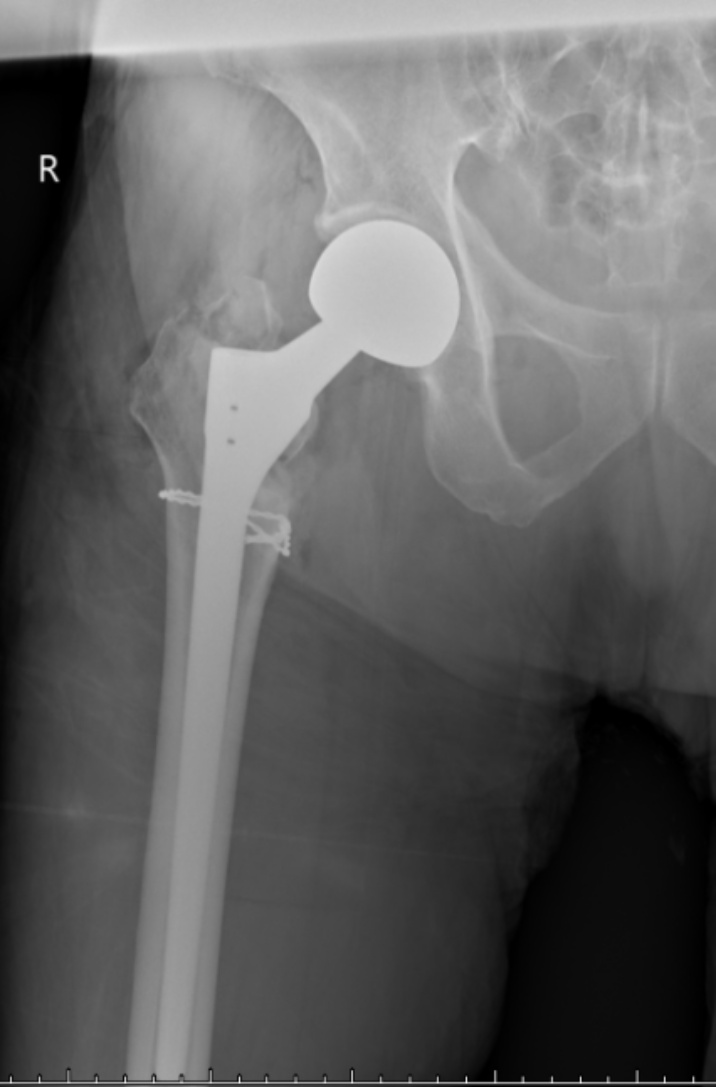

典型病例影像学表现见图1~10。图1为86岁女性右侧股骨转子间骨折(Evans Ⅲ型)患者,术前X线示骨折断端部分错位,术后X线示骨折位置可以及假体位置良好;图2显示了一名81岁男性患者,诊断为左侧股骨转子间骨折,类型为Evans V型,合并股骨干陈旧性骨折。患者接受了生物型加长柄半髋关节置换手术,并进行了股骨近端的钢丝捆扎内固定。术后X线示假体位置良好,股骨近端予钢丝捆扎固定;图3为87岁女性左侧股骨转子间骨折(Evans V型)患者,术后X线示假体位置良好,股骨大小转子骨折位置可,钢丝捆扎固定在位有效;图4为75岁女性左侧股骨转子间骨折(Evans V型)患者,术前X线示左侧股骨转子间骨折PFNA术后、骨折未愈合、内固定断裂。术后假体匹配良好,股骨近端钢丝内固定稳定可靠;图5为75岁男性左侧股骨转子间骨折(Evans IV型)患者,术后股骨大转子出现轻度位移,假体位置正常。图6为87岁男性左侧股骨转子间骨折(Evans V型)患者,给予DAA入路加长柄半髋关节置换,术前X线片,清晰地显示出左侧股骨转子间的骨折情况,术后X线影像,显示股骨的大小转子骨折位置良好,钢丝内固定装置在位稳定,假体位置良好;图7为77岁女性右侧股骨转子间骨折(Evans V型)患者,术前X线片显示右侧股骨转子间存在骨折且股骨大小转子均有累及和移位,术后X线片显示股骨小转子轻度移位,内固定装置位置稳定,假体位置良好;图8为70岁男性左侧股骨转子间骨折(Evans III型)患者,术前的X线片,清晰地显示了左侧股骨转子间的骨折情况,股骨近端髓腔钙化灶,术后假体位置满意;图9为77岁女性右侧股骨转子间骨折(Evans V型)患者,术前X线片,显示右侧股骨转子间及转子下部位骨折情况。术后假体匹配良好;图10为71岁男性右侧股骨颈骨折(Evans IV型)患者,术前X线片,显示右股骨转子间骨折的情况;术后X线表明股骨的大转子和小转子骨折位置保持良好,内固定装置稳固,术后假体位置正常。

(a) (b)

Figure 5. A 75-year-old male patient with left intertrochanteric fracture of the femur (Evans type IV). (a) Before surgery; (b) After surgery

5. 75岁男性左侧股骨转子间骨折(Evans IV型)患者。(a) 术前;(b) 术后